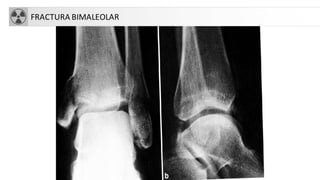

FRACTURASDE TOBILLO

• A. Fractura unimaleolar (de tibiao

peroné)

• B. Fractura bimaleolar

• C. Fractura equivalentebimaleolar

• D. Fractura trimaleolar

• TratamientoQuirúrgico: En lesiones

de dos complejos, fracturas

inestables o desplazadas. Resto: tto

conservador

FRACTURA BIMALEOLAR